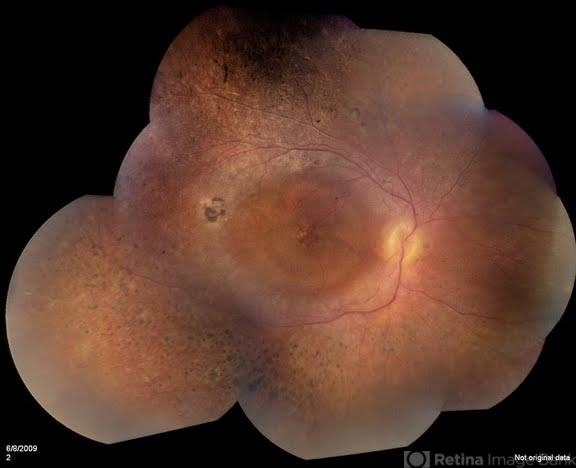

- Plaquenil Toxicity

- Patient comes in with severe vision loss in her right eye. Patient has been taking plaquenil for about 2 years. Fundus exam shows a bulls eye maculopathy centrally in the right eye.